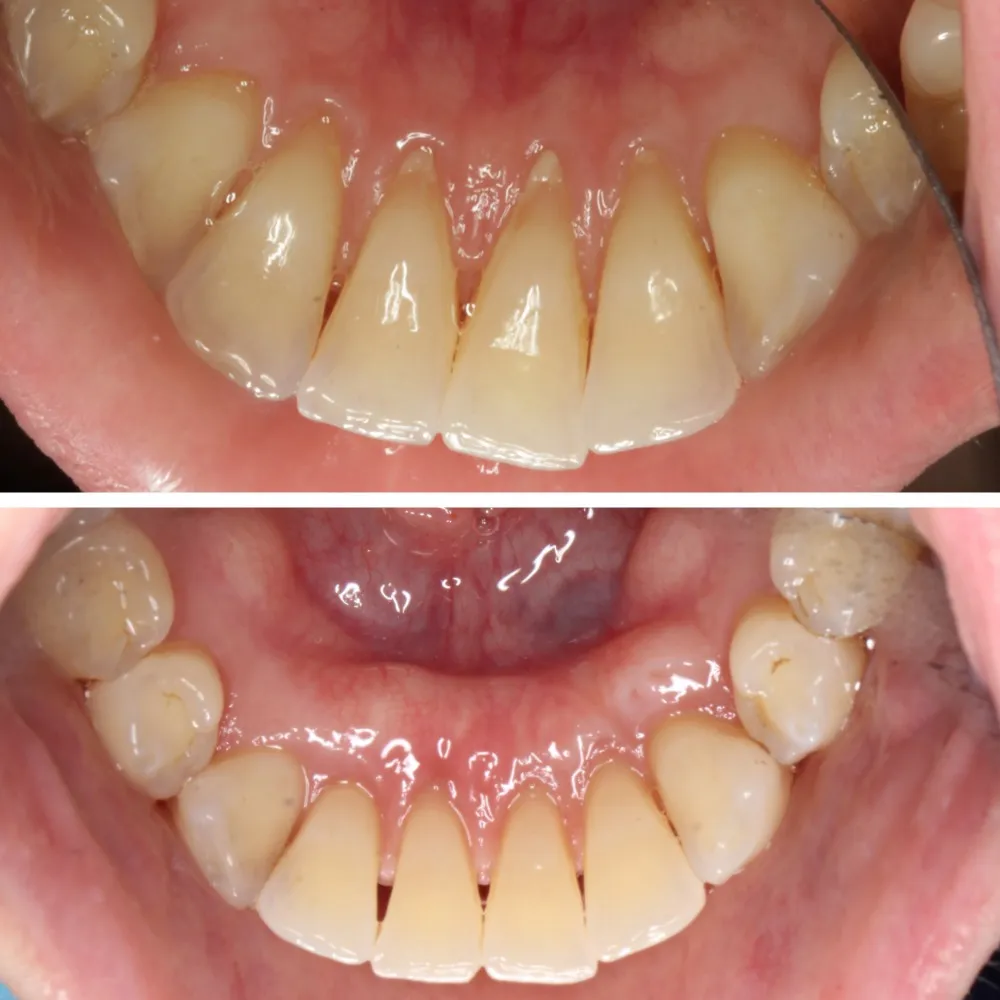

Connective Tissue Gingival Grafting for Gingival Recession